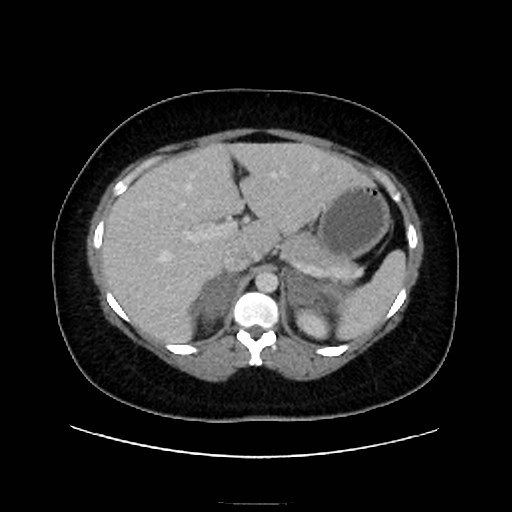

Huyết khối tĩnh mạch thượng thận (Adrenal vein thrombosis)